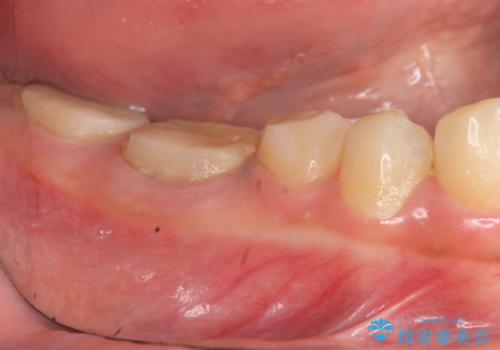

治療途中で長期間放置していたため、歯が歯ぐきから挺出(伸びてくる)してしまい、十分に強度を担保できるセラミッククラウンを装着するスペースが不足した状態です。

加えて、舌の邪魔になっている骨隆起や根尖病変といった問題を歯周外科・精密根管治療を行い、しっかりとスペースを確保したのちセラミッククラウンを作製していきます。